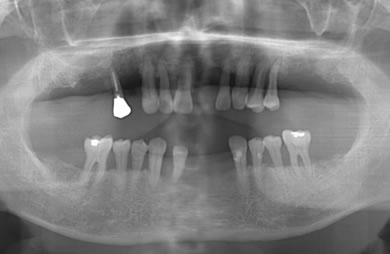

インプラントの症例写真 IMPLANT

骨再生スピードインプラント治療+AGC連結セラミック治療+セラミック治療

| 性別/年齢 | 男性 / 61歳 | ||||||||||||||||||||||||||||||||

| 主訴 | 歯周病の治療およびインプラント治療や義歯治療について相談したい。 | ||||||||||||||||||||||||||||||||

| 治療方針 | ソケットリフト法により上顎洞底部を拳上することにより、骨の無い部分に骨をつくってあげ、インプラント治療を可能にする。さらに歯周病により組織の破壊が著しいので、AGC連結セラミック治療により上顎の審美的回復を行う。 | ||||||||||||||||||||||||||||||||

| 治療内容 | インプラント7本(抜歯AGC即日スピードインプラント+ソケットリフト)、AGCハイブリッドセラミック連結ブリッジ1装置(上顎)ハイブリッドセラミック8本 | ||||||||||||||||||||||||||||||||